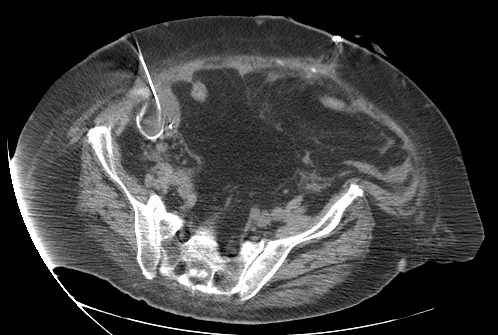

Abscess Drainage: Case 1

23 year old female with fever and RLQ tenderness s/p appendectomy.

Comment: This case demonstrates performance of a straight-forward CT-guided drainage. Once the abscess was localized on CT and the access site confirmed with a 25g needle, the collection was accessed with a Chiba needle and a guidewire was coiled within the collection. Serial dilatation was then performed so that a pigtail drainage catheter could be placed within the collection for drainage.